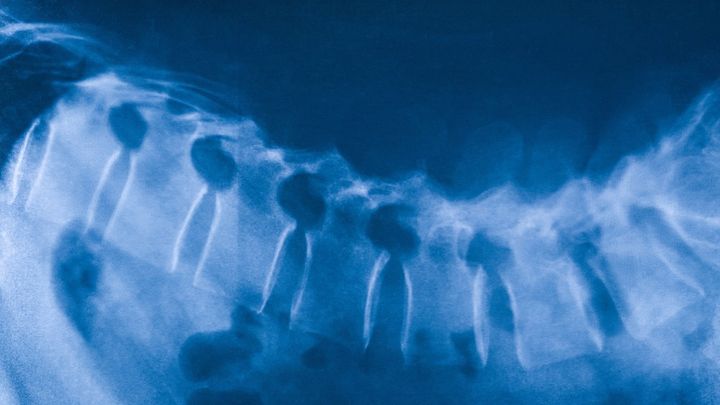

脊椎が切れたラットが「人工培養脊髄」の組み込みで再び歩けるように / Credit:Canva